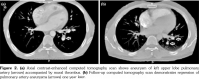

Chest X-ray showed left parahilar opacity (Figure 1). Pulmonary computed tomography (CT) angiogram revealed PAA with thrombus (Figure 2a). Bronchoscopy revealed no origin of bleeding. Echocardiography demonstrated mobile thrombus in the right ventricle (Figure 3a). Blood and urine cultures were sterile. Venereal Disease Research Laboratory test, tuberculosis tests, human immunodeficiency virus serology, antiphospholipid antibodies, anti-nuclear antibodies, and anti-neutrophil cytoplasmic antibodies were negative. Hereditary coagulation thrombophilic factors were normal.

The patient was treated with pulse steroid (intravenous methyl prednisolon 1 g/d for three days), intravenous cyclophosphamide (1 mg/kg/d), peroral azathioprine (125 mg/d) and peroral colchicine 0.5 mg/d. Peroral prednison was given after intravenous methyl prednisolon. Anticoagulation therapy was not administered. Patient was followed-up to one year. Reevaluation with pulmonary CT angiograms and echocardiograms demonstrated a remarkable regression of PAAs, and organization of intracardiac thrombus (Figures 2b and 3b, respectively). Currently, the patient is in a stable condition without hemoptysis or embolic event.